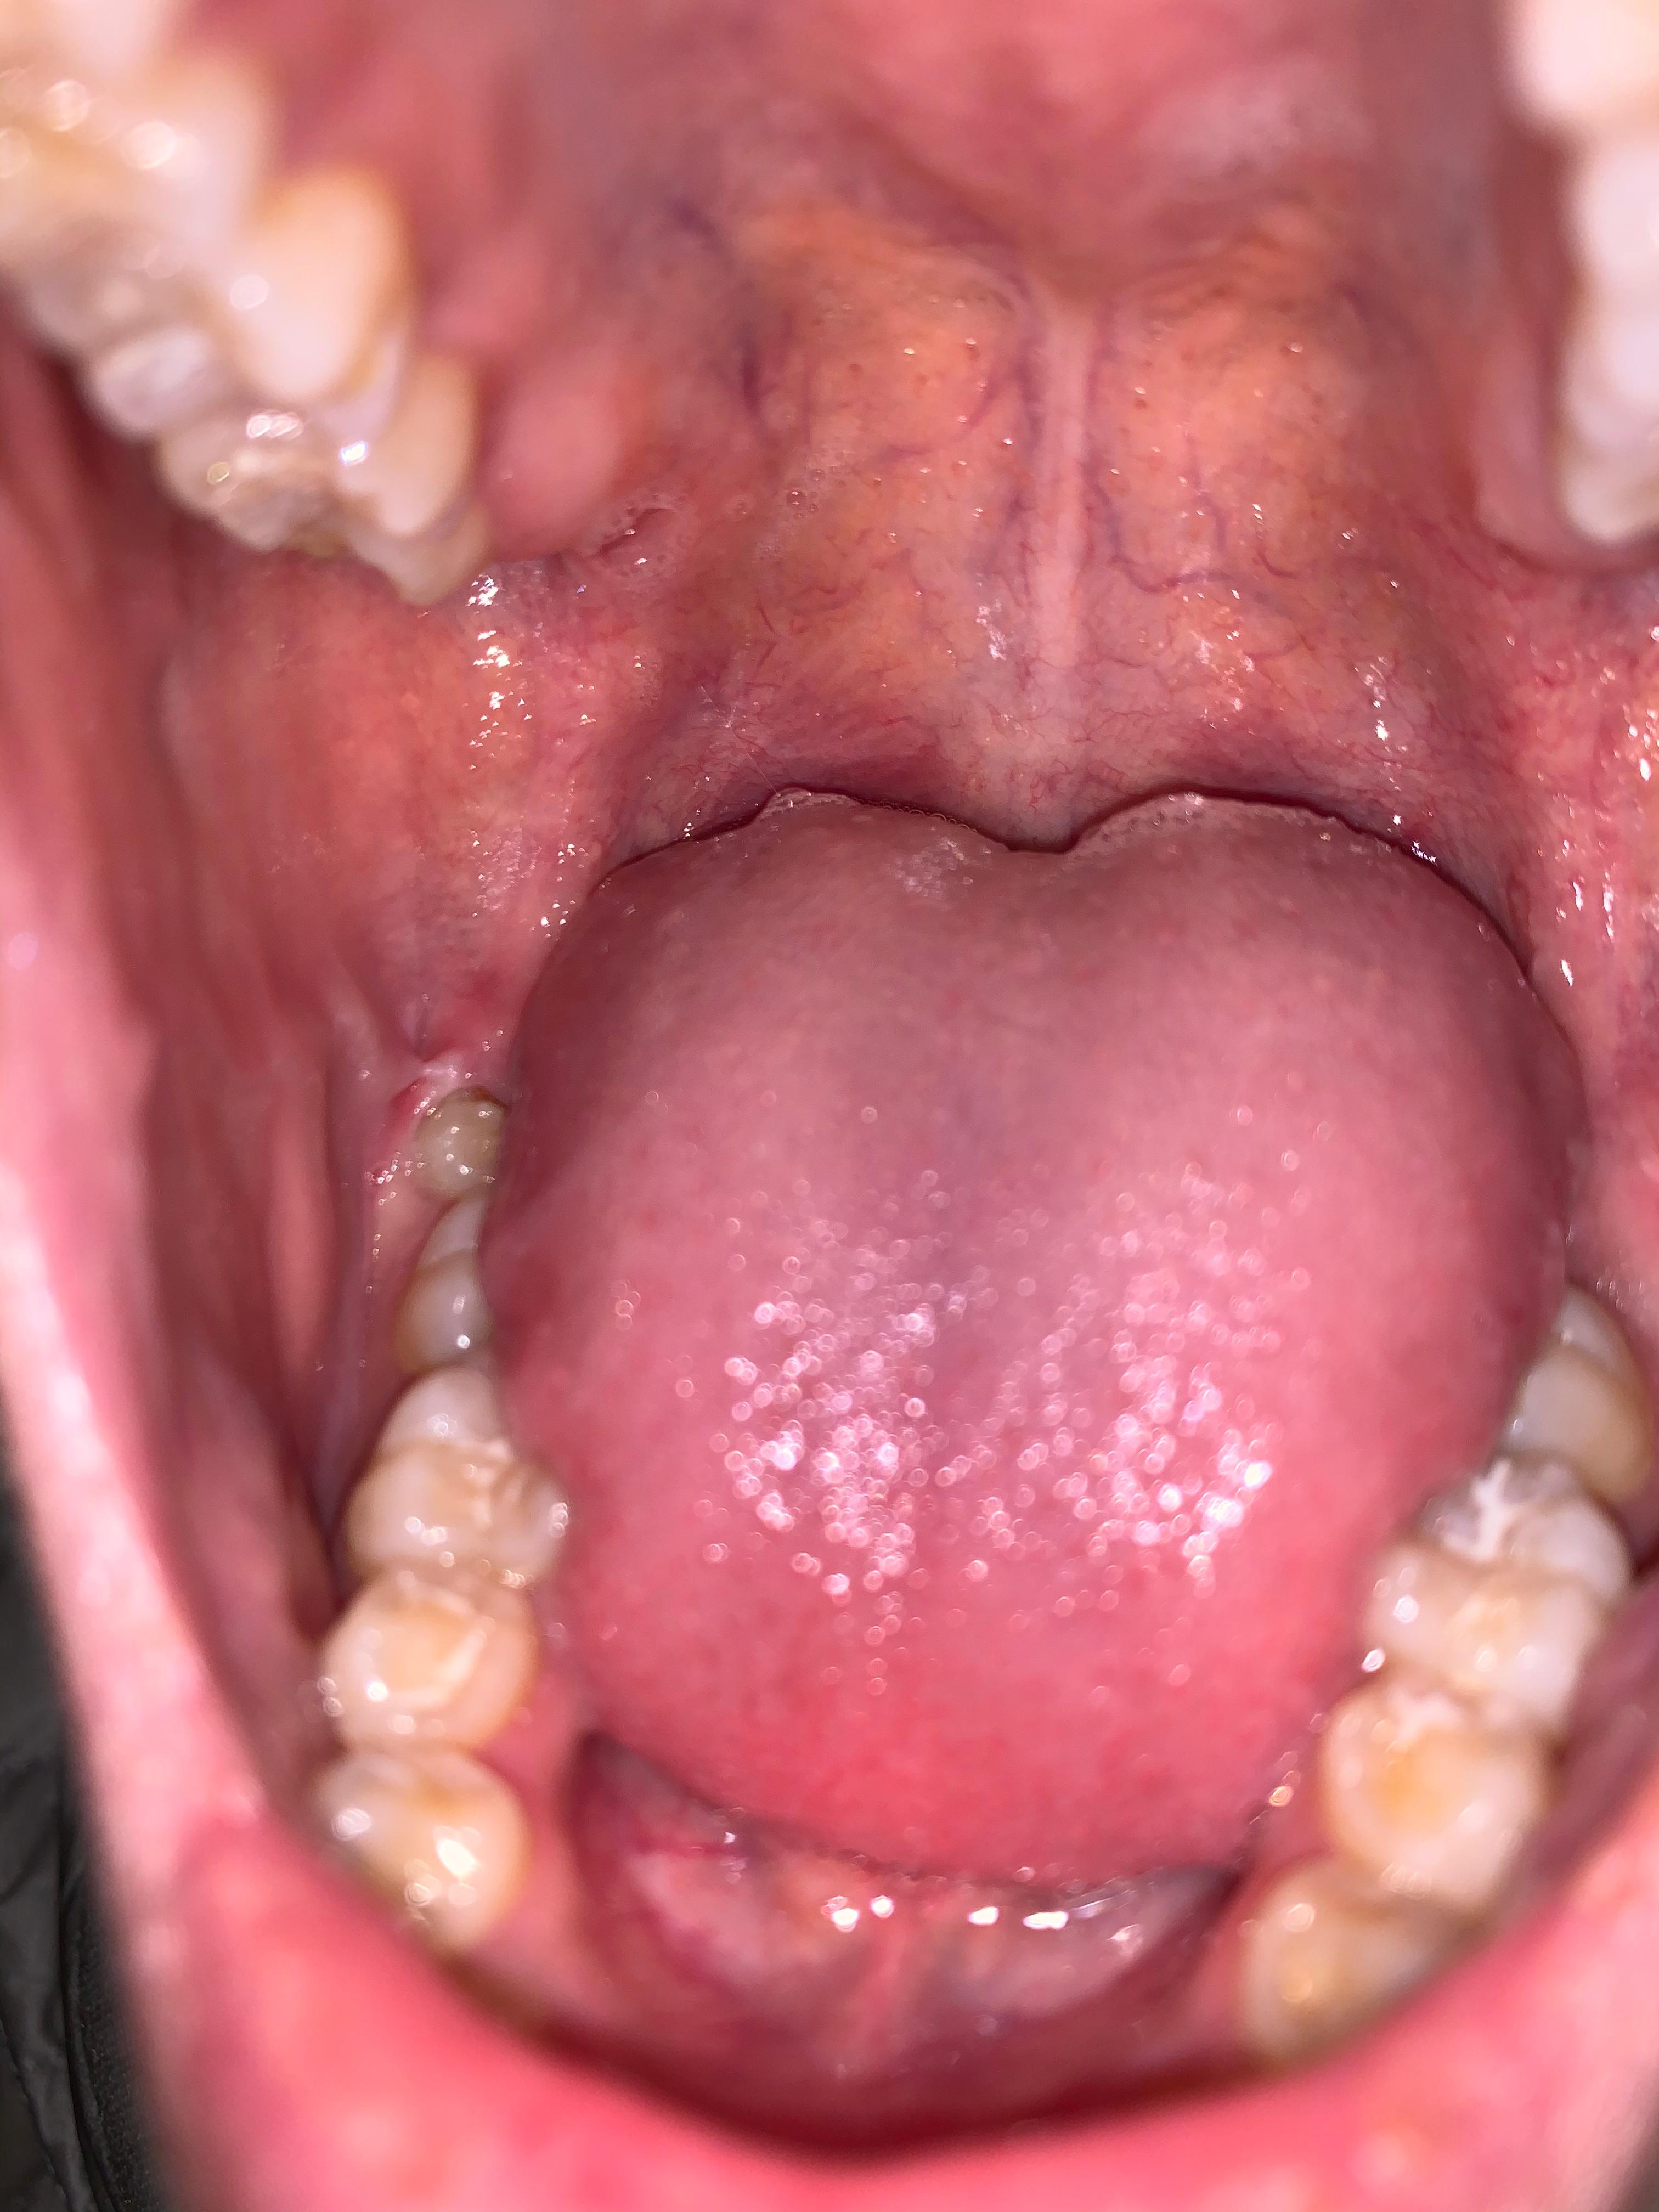

Beule am zahnfleisch ohne schmerzen. Die braucht sie dann auch. In diesen Fällen sollte man am besten zwei bis drei Tage abwarten und schauen ob sich die Situation bessert. Das sieht nach einer stark entzündeten Zahnfleischtasche aus.

Am Zahn und Zahnfleisch können viele Probleme entstehen. Die beuele ist vermutlich ein sich ausbildender abszeß der von alleine nicht besser wird auch die schmerzen werden nicht besser. Der wird die Stelle behandeln und ihr wahrscheinlich Antibiotika verschreiben.

Weitere Auslöser können sein. Eine Eiterbeuleentsteht durch die Entzündung im Knochen und am Zahn. Probleme am Zahn wie Zyste Fistel Eiter Schwellung.

Zahnentzündung apikal bedeutet dass sich die Entzündung an der Wurzelspitze befindet. Das Anschwellen vom Zahnfleisch und evt. Wenn die Wurzel am Zahn entzündet ist macht sich dies meist bemerkbar durch die Schmerzen und ein leichtes anschwellen vom Zahnfleisch.

Dehnt sie sich bis zum Kieferknochen aus heißt. Deshalb empfindet der Betroffene keine Schmerzen obwohl sich die Entzündung mit großer Wahrscheinlichkeit schon tief in den Kiefer hinein vorgearbeitet hat. Ein traumatischer Zahnunfall oder eine Verletzung.

Entweder wurde das Zahnfleisch durch mechanische Reize verletzt oder eine Infektion mit Viren Bakterien oder Pilzen ist schuld an der Entzündung. Die Beule ist unnachgiebig aber sie ist ja noch ein Kind. Diese Bakterien können einen Abszess verursachen selbst wenn die Zähne gesund und frei von Löchern sind.

Mit der richtigen Betäubung ist die Behandlung vom Zahn ohne Schmerzen. Eine Schwellung des Zahnfleisches ist ein Anzeichen für eine Entzündung.